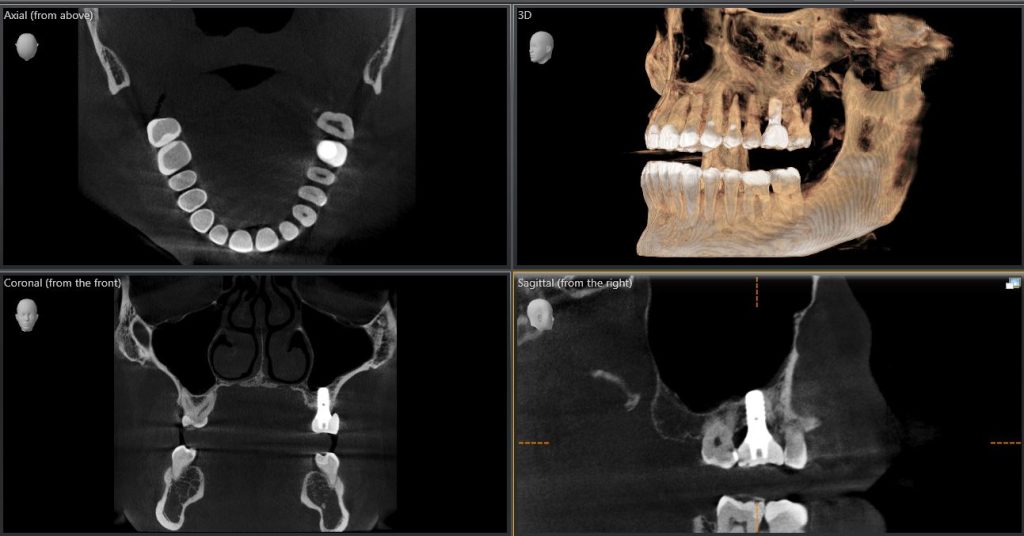

3D imaging, or Cone Beam Computed Tomography (CBCT), is a medical imaging technique that uses X-rays to create a 3D rendering of the maxillary and mandibular jaws, including the TMJ in most cases. For the first time, we are able to see bone, teeth, and sinuses in three different planes.